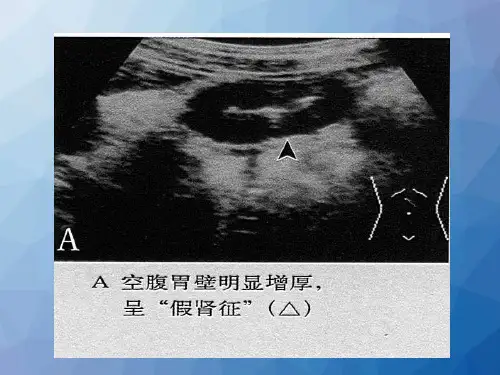

幽门部

十二指肠球部

胃体部